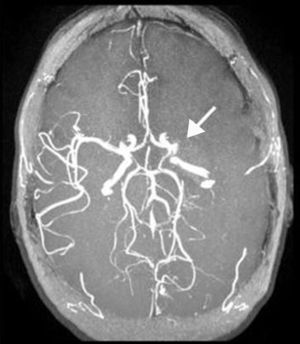

Caso clínicoMujer de 28 años, oriunda de Brasil, diestra. Sin antecedentes de FRCV clásicos, utilizó parches de etinilestradiol como anticonceptivo en el año previo a la consulta, sin uso de otras medicaciones ni consumo de tóxicos. Ingresó al departamento de emergencias por afasia mixta, hemianopsia homónima derecha y paresia facio-braquio-crural derecha de instalación súbita. En el examen se constató una escala de NIHSS de 16 puntos. Se realizó tomografía axial computarizada (TAC) de encéfalo, donde se evidenció leve borramiento del ribete insular y ganglios basales izquierdos, junto a hiperdensidad espontánea en M1 izquierda. Se comenzó trombólisis intravenosa a las 2 h y media de iniciados los síntomas, la cual finalizó sin complicaciones. La TAC de control a las 24 h y la resonancia magnética (RM) (realizada al quinto día del evento) confirmaron el infarto en el territorio de la arteria cerebral media izquierda, con compromiso de ganglios basales, corteza fronto-insular y corteza temporal lateral. En la angio-RM se evidenció amputación a nivel de M1 izquierda y circulación colateral leptomeníngea (figs. 1 y 2).